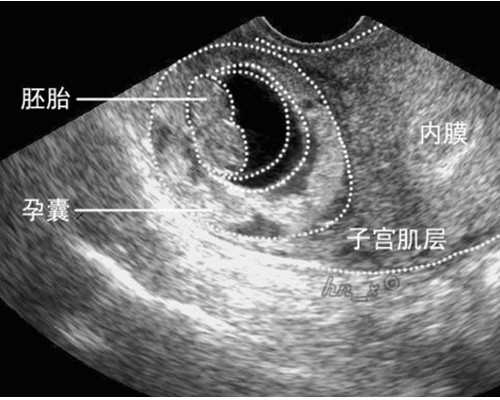

试管婴儿专家指出,在自然怀孕过程中,精子和卵子是在母体内的输卵管中完成受精,受精卵边分裂边移动到子宫内着床发育。试管婴儿则不同,它是一项体外受精,操作过程中需首先将精子和卵子取出,在体外人工控制的环境下进行受精结合,培养3~5天后形成早期胚胎再移植回母体子宫内。但当胚胎回到宫腔之后,其着床、发育、成长的过程和自然怀孕就没有区别了,也需要妈妈通过十月怀胎才能分娩。

而自然受孕是指,进入阴道的精子经过重重关卡,宫颈粘液、宫腔,在性交高潮时,通过漏斗状宫角括约肌的松弛及肌肉蠕动的吸引作用,将精子经输卵管的间质部吸入峡部,在输卵管内与卵子相遇并完成受精,卵子受精后要在输卵管的壶腹部停留2~3天的时间,然后由输卵管的蠕动把形成的胚胎送回女性子宫,继而着床,发育成胎儿。